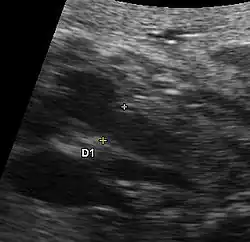

Aspects échographiques avant la naissance

Plusieurs aspects peuvent se rencontrer: une hypertrophie ou une hypoplasie du ventricule gauche ou un ventricule gauche quasiment sans aucune contraction sans aucun flux sanguin au doppler. La circulation du sang étant alors uniquement assuré par le ventricule droit. Le pronostic de cette maladie dépendra du ventricule droit. La visualisation directe d'une ouverture incomplète de la valve aortique et la présence de turbulence au niveau aortique par doppler couleur sont les deux signes directes de cette pathologie mais difficiles à visualiser lors de l'échographie obstétricale. Une brillance anormale du ventricule gauche est un signe de souffrance myocardique par diminution du flux sanguin des coronaires.